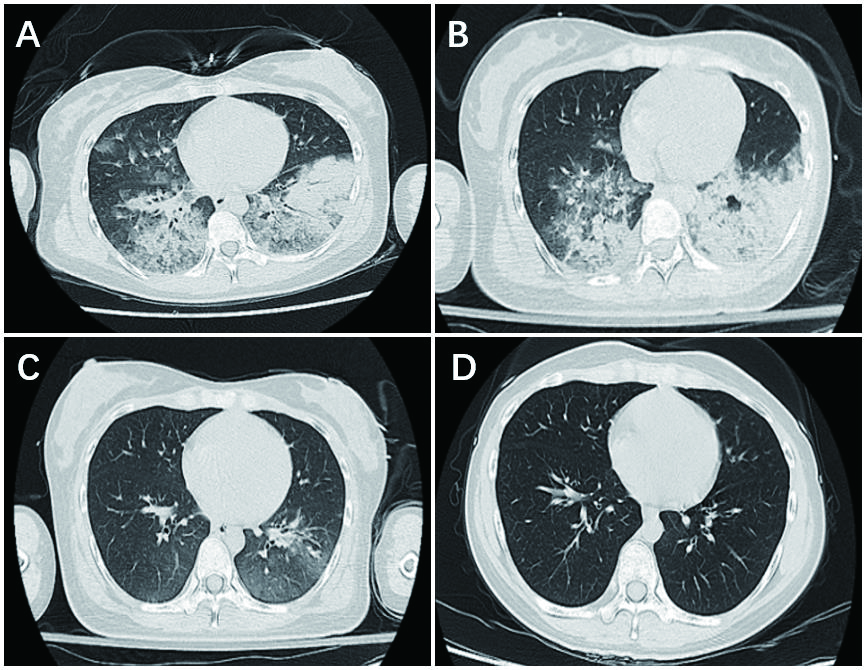

患者女,24岁,因“咳嗽4 d,发热2 d,胸闷气急2 h”于2018年6月14日收入急诊科。患者4天前无明显诱因下出现干咳,2天前出现发热,自测体温39℃,至当地诊所就诊,诊断呼吸道感染,在头孢西丁皮试阴性后予头孢西丁钠2 g加入生理盐水250 mL静滴(滴速50滴/min)及布洛芬混悬液15 mL口服后体温下降至正常。6月14日患者起床后感头晕恶心,再次至当地诊所静滴头孢西丁钠,约5 min后患者出现头晕恶心咳嗽等症状加重,伴冷汗,胸闷心悸,呼吸困难,全身无皮疹,测血压未测出,脉搏细弱,考虑注射头孢西丁钠引起过敏性休克,立即停止输液,予肾上腺素2 mg皮下注射后转至本院。入院查体:T 38.5℃, BP 87/53 mmHg(1 mmHg=0.133 kPa),P 122次/min,R 25次/min,血氧饱和度为85%,神志清,面色苍白,双肺可闻及湿啰音。心律齐,未及病理性杂音。腹软,无压痛和反跳痛。双下肢无水肿。辅助检查:急诊血气分析提示pH 7.314,PO2 126 mmHg,PCO2 30.3 mmHg,BE -9.7 mmol/L,SB 16.8 mmol/L,全血乳酸5.6 mmol/L。血白细胞10.6×109/L,中性粒细胞79.2%,嗜酸性粒细胞0.1%。C反应蛋白56.1 mg/L,降钙素原0.336 ng/mL。肌酐91 μmol/L,肌钙蛋白-I 1.106 ng/mL,NT-proBNP 277.95 pg/mL,总IgE 280.6 U/mL,血钾2.5 mmol/L。胸部CT示两肺弥漫渗出伴小叶间隔增厚,左肺下叶局部实变不张(图 1A)。初步诊断:①过敏性休克;②重症肺炎急性呼吸窘迫综合征。立即予储氧面罩吸氧,亚胺培南西司他丁钠、甲泼尼龙静脉应用,去甲肾上腺素维持以及抗组胺补液等治疗,但患者呼吸仍急促,最快50次/min,为进一步治疗收住综合ICU。

| 图 1 患者的胸部高分辨CT检查。A:入院当天;B:入院后1 d;C:入院后4 d;D:出院后14 d |

入综合ICU后给予患者无创呼吸机辅助通气,继续甲泼尼龙静脉应用,6月15日复查胸部CT示两肺弥漫渗出伴小叶间隔增厚,两肺下叶局部实变不张,较前片(2018-06-14)稍吸收好转。考虑患者肺部感染仍严重,予加用美罗培南及莫西沙星静滴抗感染。但是患者病情无改善,不能平卧,且血肌酸激酶、肌钙蛋白-I和NT-ProBNP均较前升高,心超提示左室节段性运动减弱,左心功能减低,考虑并发急性心肌炎,予气管插管,呼吸机辅助通气。6月18日复查胸部CT示两肺多发炎症,较前片(2018-06-15)明显吸收好转(图 1C)。予停用甲泼尼龙,拔除气管插管,转入感染性疾病科病房继续治疗,予口服莫西沙星治疗1周后出院。出院后2周患者复查胸部CT示右肺中叶少许纤维灶,左下肺少许渗出,较前(2018-06-18)明显吸收(图 1D)。